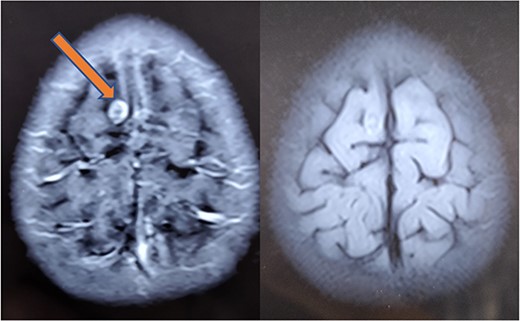

The histopathology report revealed the presence of a parasite composed of cuticle, subcuticular cells along with muscle, and chronic inflammatory infiltrate with a final impression of cysticercosis (Fig. 5). After this diagnosis, we reevaluated our history with more details. There was no history of headaches, seizures, or visual difficulties. The patient was found to be a vegetarian in diet. A pediatric physician evaluation was also done where a contrast-enhanced computed tomography (CECT) brain and ophthalmic examination were advised to evaluate for a possibility of neurocysticercosis. The ophthalmic examination was within normal limits, but the CECT showed a hypodense area in the right frontal lobe (Fig. 6). On further correlation with contrast MRI, a ring-enhancing lesion in the right paramedian frontal lobe surrounded by non-enhancing vasogenic edema was seen. Another small lesion was seen in the right external capsule surrounded by minimal edema (Fig. 6). Both lesions appeared to be granulomatous, giving an impression of neurocysticercosis. The child was treated with syrup albendazole 15 mg/kg per day in two divided doses for 1 month. A short course cover of dexamethasone 0.1 mg/kg per day started 1 day before albendazole was started, continued for a month, and then tapered over a week.

CT (left) showing a hypodense lesion in the right frontal lobe, T1 post-contrast MRI image (center) showing a ring enhancing lesion in the right frontal lobe and FLAIR image (right) showing non-enhancing vasogenic edema surrounding the lesion.

At 1-month follow-up, the patient had complete resolution of pain and swelling. Local USG back showed no evidence of any remnant lesion. At the 6-month follow-up, an MRI of the brain was done that showed a major reduction in the size of the lesion and resolution of perilesional edema (Fig. 7). At 1-year follow-up, the patient was found to be completely symptom-free, managing his activities of daily life, very well.

Repeat MRI at 6 months showing resolved changes with reduction in size of the lesion with resolution of perilesional edema.